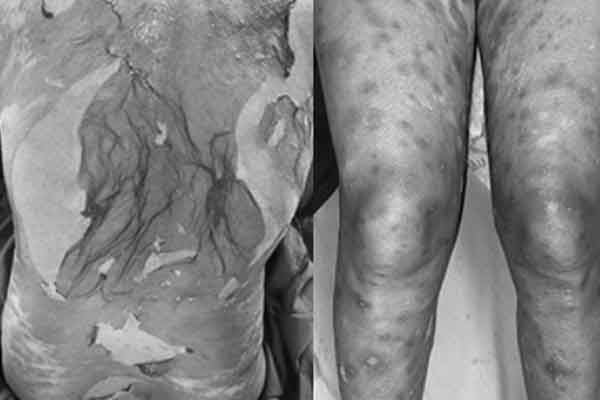

Ông L. suýt bị cắt cụt bàn chân trái, đe dọa tính mạng vì hệ quả của việc dùng thuốc không rõ nguồn gốc. Ảnh: Bệnh viện cung cấp

Theo chia sẻ của người bệnh, để giảm các triệu chứng sưng, viêm của bệnh gout, ông L. thường mua thuốc nam có chứa thành phần corticoid không rõ nguồn gốc về tự điều trị. Sau một thời gian, tình trạng bệnh chuyển biến nặng.